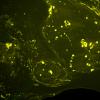

1C1 Amyloid (Case 1) Thio-S Image_01 - Copy

1C2 Amyloid (Case 1) Thio-S Image_03 - Copy